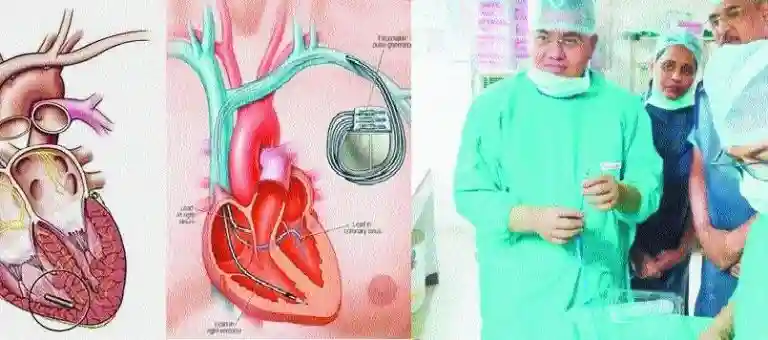

82-year-old man first from Central India to get pacemaker implanted

Parents of a 27-year old man from Virar, who suffered a brain haemorrhage, donated his vital organs to four critically ill patients.Dr Nitin Tiwari conducts procedure that is done first time in Central India, Senior Cardiologist in a Heart Hospitals in Nagpur performed first of its kind procedure of Central India where he implanted a leadless pacemaker in a senior citizen from Madhya Pradesh (MP). This procedure was a life saver for the patient who had run out of options to survive. The procedure is an added achievement to the long list of firsts in Central India by Wockhardt team. An 82-year-old patient had been in heart failure for several months and he required a Pacemaker to keep his heart beating. As the efforts of cardiologist at MP did not yield any result, but developed infection in chest. The patient’s relatives came to Wockhardt hospital and consulted Dr Nitin Tiwari, Senior Consultant – Interventional Cardiologist. After thorough examination, history taking and careful consideration, the patient was suggested for a leadless pacemaker (MICRA). In this instance, MICRA being a leadless pacemaker, the need for skin pocket was not there and hence the chances of pocket infection are negligible, pointed out Dr Nitin Tiwari. The miniaturised leadless pacemaker ‘MICRA’ is the world’s smallest pacemaker and is delivered directly to the heart. It is also 93% smaller than conventional pacemakers, has a mass of 1.75 gm and volume of 0.8 cc. The traditional method of pacemaker impant is done usually by creating a pocket near chest and placing a small metal container housing a battery and the electrical circuitry that regulates the rate of electrical pulses sent to your heart. One to three flexible, insulated wires are each placed in a chamber, or chambers, of your heart and deliver the electrical pulses to adjust your heart rate. Dr Tiwari pointed out, “With conventional pacemakers the risk of pocket infection varies from 1.6 to 2.2 per cent. Usually the risk is more in the second time implantation. The chances of infection are more in diabetics, young males, multiple lead pacemakers and immune-compromised people.” Dr Tiwari also advised patients to undertake pacemaker implantation preferably at a high volume centre so as to decrease the chances of infection. K Sujatha, Centre Head added, “Wockhardt Heart Hospitals has completed 15 years in Nagpur during that time it has performed more than 25,000 procedures and has seen many one of its kind procedures and surgeries. We have Cardiac specialist who have more than 20 years of experience in this field. Dr Nitin and team did excellent work.” Source : http://thehitavada.com/Encyc/2018/12/27/City-Cardiologist-implants-smallest-pacemaker-successfully.aspx Source : https://timesofindia.indiatimes.com/city/nagpur/82-yr-old-man-first-from-central-india-to-get-leadless-pacemaker-implanted/articleshow/67262971.cms